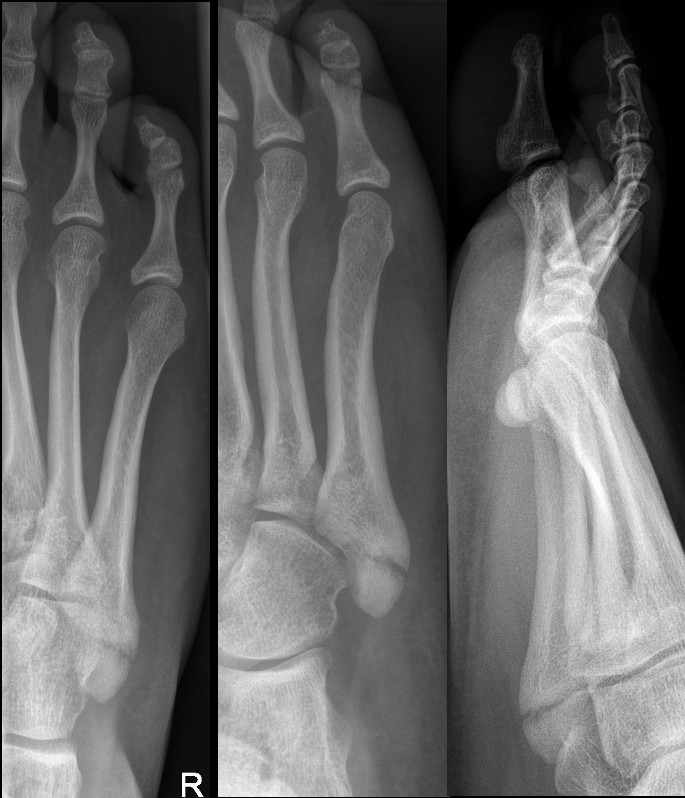

Avulsion fracture at the base of the fifth metatarsal (insertion of peroneus brevis)

Fracture of base of 5th metatarsal follow inversion injury

- CAM boot weight bearing as tolerated with Fracture Clinic follow up in 1 week.

- It is important to differentiate avulsion fractures of the base of the fifth metatarsal with Jones fractures which involve the 4th and 5th inter-metatarsal joint.

- These intra-articular fractures are managed in a below knee backslab non weight bearing with crutches and Fracture clinic follow-up in 1 week.

Angulated Salter-Harris II fracture of 5th proximal phalanx

Dorsally displaced transverse fracture of neck of 3rd proximal phalanx

- Consider reduction if significantly angulated.

- Buddy strap and Darco walking shoe or sturdy shoes with no specific follow up.